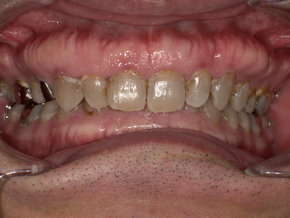

症例紹介(50代男性)

治療前の口腔写真。下顎後退により気道が狭くなっている様子